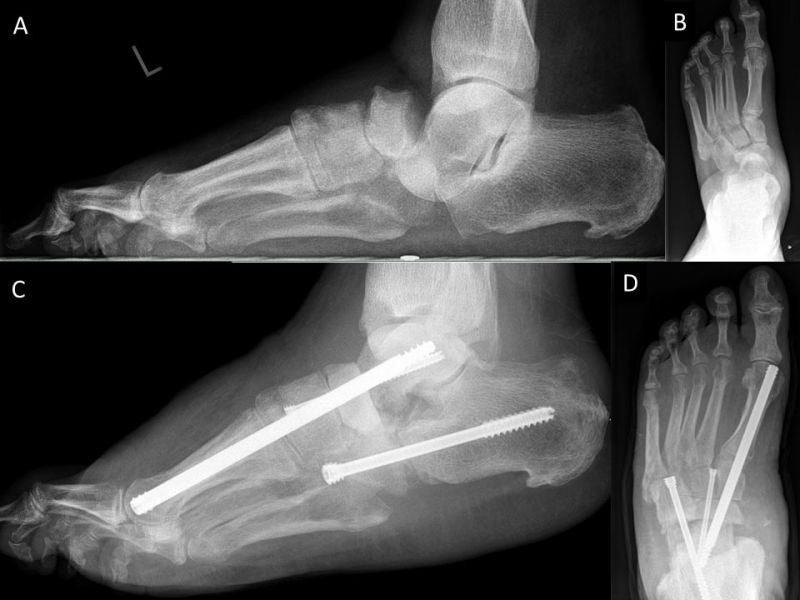

- Operative Behandlung von Druckstellen durch den Zusammenbruch des Fußlängsgewölbes

Als Folge der diabetesbedingten Neuropathie kann es zu dem sogenannten Charcotfuß kommen. Bei dieser Komplikation der Diabeteserkrankung kommt es häufig zu einer Zerstörung der Fußwurzelgelenke und -knochen. Dabei springen die Knochen aus den Gelenken (Luxation) und brechen (Fraktur). Der Fuß verliert an Halt und das Fußgewölbe kann zur Fußsohle durchbrechen (Plattfuß). Hierbei treten Druckstellen durch überstehende Knochenfragmente an der Fußsohle auf, die dann zu Hautschäden führen. Sollten hier konservative Therapiemaßnahmen (Polsterung/Schuhzurichtung) versagen, ist eine operative Korrektur angezeigt. Dabei werden die Knochen mittels Platten und langen Schrauben stabilisiert.

Zum Lesen der Bildbeschreibung und Vollansicht bitte Bild anklicken. Fotos: Alexander Mehlhorn

- Operative Behandlung von Druckstellen durch Fehlstellungen/Instabilität des Rückfußes bzw. Sprunggelenk

Eine weiterer typischer Verlauf eines Charcot Fußes betrifft die Zerstörung der Bänder und des oberen Sprunggelenks. Der Fuß knickt dabei nach innen, manchmal auch nach außen weg. In Schuhen kommt es meist zu Druckstellen im Bereich des Knöchels. Teilweise ist das Sprunggelenk ist so instabil, dass Laufen nicht mehr möglich ist. Oft sind hier die Möglichkeiten einer konservativen Therapie mit Polsterung/Schuhversorgung nicht mehr ausreichend. Kann der Fuß von außen nicht mehr ausreichend stabilisiert werden, ist eine operative Stabilisierung der abgekippten Gelenke mit Platten und Schrauben notwendig um wieder einen belastbaren Fuß zu erreichen.